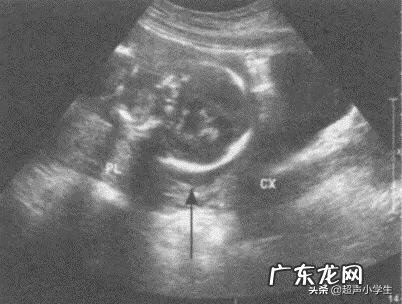

28周以前,胎盘下缘距宫颈内口小于20mm,成为胎盘前置状态 。28周以后,胎盘下缘距宫颈内口小于20mm,成为前置胎盘 。而且在产检时候会作超声检查,可以通过此项检查被发现 。